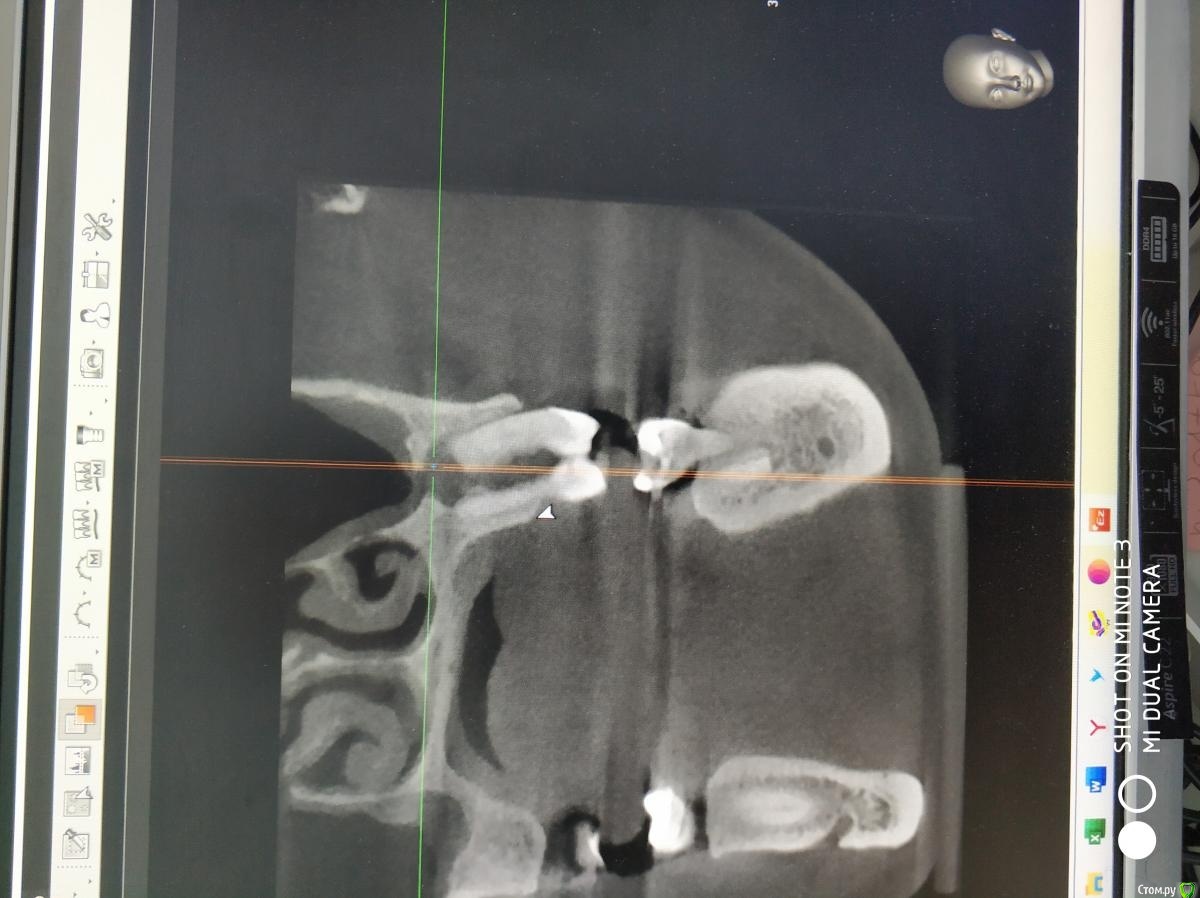

Raystom Опубликовано 20 февраля, 2021 Поделиться Опубликовано 20 февраля, 2021 Обратилась пациентка с неприятными ощущениями в области зубов 26, 27, во рту эти зубы показались мне темнее остальных, на КТ видна вот такая красота. Каков план лечения в таких ситуациях? Попробовать отделить пазуху от грануляций или просто удалить и после лечения ЛОРа идти на закрытие ОАС? Как после восстанавливать кость? И какие временные промежутки. Понимаю, что многие скажут при таких вопросах передать другим, но это не мой вариант. Мб есть литература по подобным случаям? Ссылка на комментарий

Карен Аванесов Опубликовано 22 февраля, 2021 Поделиться Опубликовано 22 февраля, 2021 Обратилась пациентка с неприятными ощущениями в области зубов 26, 27, во рту эти зубы показались мне темнее остальных, на КТ видна вот такая красота. Каков план лечения в таких ситуациях? Попробовать отделить пазуху от грануляций или просто удалить и после лечения ЛОРа идти на закрытие ОАС? Как после восстанавливать кость? И какие временные промежутки. Понимаю, что многие скажут при таких вопросах передать другим, но это не мой вариант. Мб есть литература по подобным случаям?Аккуратно удалить, убрать грануляции, инструментально уточнить есть ли сообщение с пазухой (Думаю что нет), если и есть, коллаген, и лунку ушит. Динамичный контроль. Ссылка на комментарий